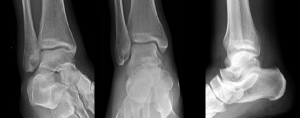

Photos: Arun Sayal, MD, CCFP(EM)

• Tips for Catching Commonly Missed Ankle Injuries